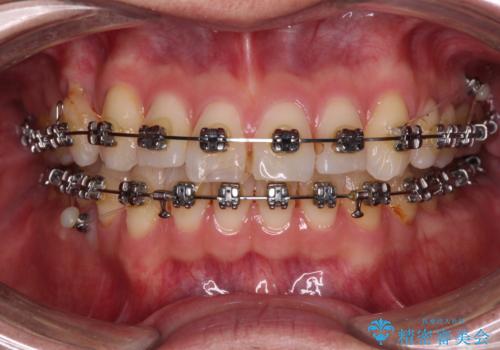

- 矯正装置

- メタルブラケット

咬合平面改善のため、アンカースクリューを多用し、ワイヤー装置にて矯正治療を行うこととしました。